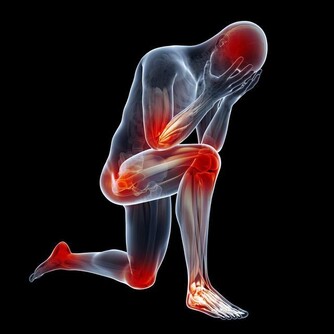

10.易發生肌肉痙攣: 久坐使血流不暢,肌肉僵硬、痠痛、萎縮,使肌肉失去力量和彈性而發生痙攣。 11.會引起腰背疼痛: 久坐使得整個軀體重量全部壓在腰骶部,使腰背肌長期處於緊張狀態。

12.女性久坐更易得3種癌: 研究發現,久坐對女性的傷害遠高於男性,它容易導致女性患癌,特別是乳腺癌、卵巢癌、多發性骨髓瘤的風險上升。 因此,請不要久坐!要經常起來活動活動。凡因工作需要久坐的人,每隔兩小時,應進行一次約10分鐘的活動,或自由走動,或做簡單運動操等。平時,也應多晨跑、散步、做健美操等,以避免疾病發生。